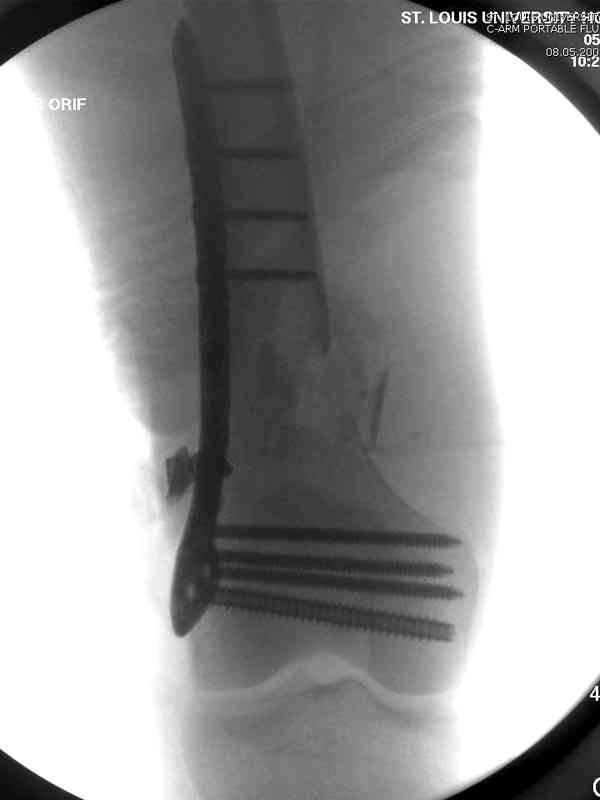

The patient with non-union of the distal femur

Больная К. с тугим ложным суставом н/3 бедра. Травма в 2005 г.-закрытый перелом, остеосинтез в аппарате Илизарова. В 2006 г. оперирована по поводу несросшегося перелома.

В ноябре 2006 г. демонтаж аппарата, после чего в течении месяца развилась вальгусная деформация. Имеется патологическая подвижность. Объем движений в коленном суставе 180-140. На обсуждение выносятся варианты лечения погружными конструкциями.

The patient with non-union of the distal femur. Trauma in 2005 - closed fracture of the femur, external fixation with Ilizarov apparatus. Non-union. In 2006 open reduction and external fixation with Ilizarov apparatus. In November 2006 the apparatus was removed, after that valgus deformation developed. There is pathological mobility. The knee motion 180-140. We'd like to discuss options of internal fixation.